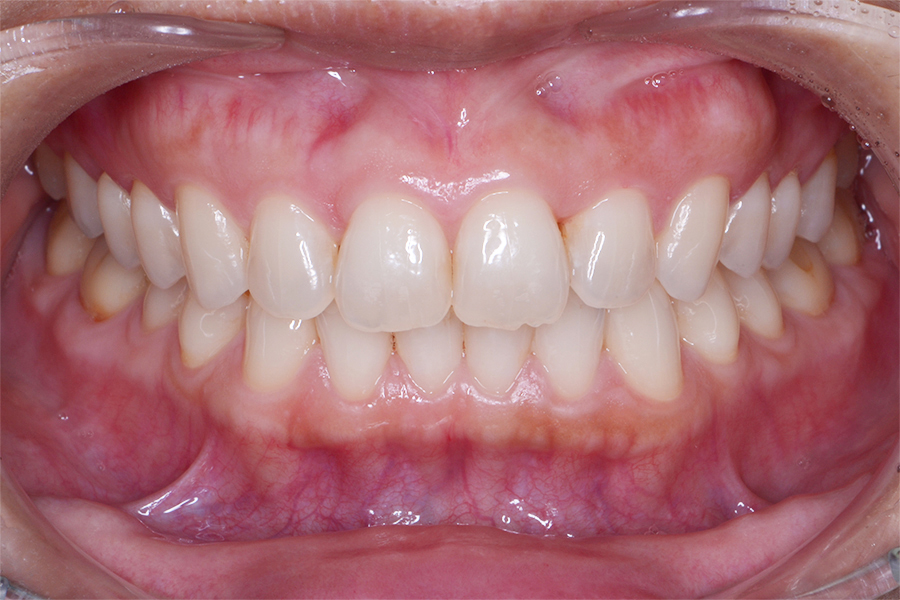

【20代女性】すきっ歯(隙間)と

咬み合わせを良くしたい

【矯正歯科治療】

- 担当医

- 三留先生

- 主訴

- すきっ歯(隙間)と咬み合わせを良くしたい

- 期間

- 治療期間10か月

- 費用

- 治療費35万+20万(別途調整料)

- 治療内容

- ハーフリンガル矯正(上顎裏側・下顎表側矯正)

- 治療に伴うリスク

- 後戻り